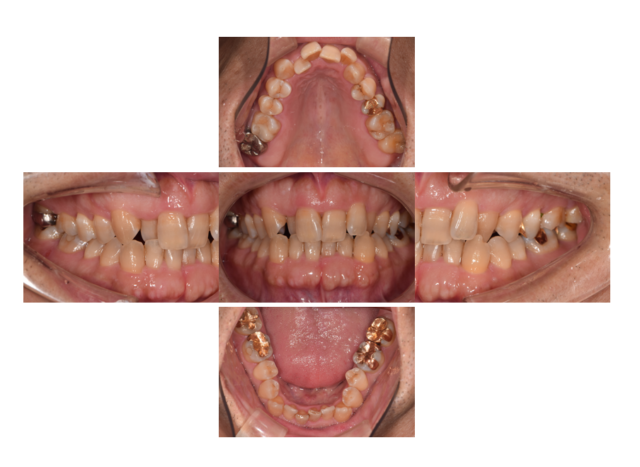

主訴:歯並びが悪く抜けて見える

Before

通院時の年齢 | 55歳 |

---|---|

性別 | 男性 |

通院回数 | 20回程度 期間1年半 |

通院目的 | ワイヤー矯正では歯が痛くなりインビザラインを用いた痛くない矯正をしたい |

処置内容 | インビザライン |

費用 | 費用80万(月々管理費用5500円) |

デメリット・注意点 | 移動がスムーズに行われない場合は追加でねじを埋入して移動を促す場合がある 多少なりとも歯が動く際は痛みがある 20時間以上の装着時間が必要 |

備考 | 歯並びは見た目だけでなく咬むことの健康とご自身の歯を長持ちさせることに役立ちます |